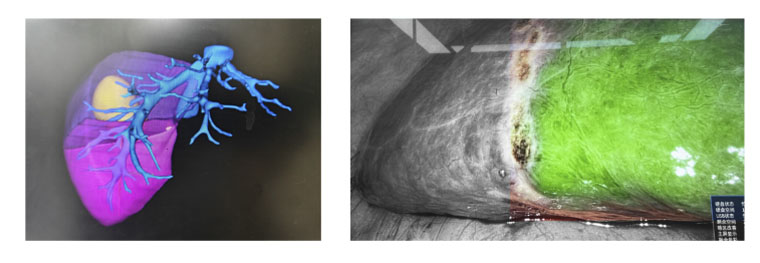

三维导航助力精准医疗

在CT磁共振科的支持下,肝胆外科将荧光显影技术与肝脏三维重建技术相结合,构建了一套从术前到术中的精准导航系统,让医生告别了术前依靠二维影像制定手术计划的时代。

患者肝右后叶肝癌,根据三维重建精准阻断右后肝蒂,获得缺血线后进行荧光反染,显示肝脏切面的荧光和非荧光界面,助力解剖性肝右后区切除。

三维重建技术直观呈现肝段划分及血管、胆管解剖关系,而荧光显影技术则通过肝段染色,全程显露段间静脉,有助于识别肝内肝段间的界限,使肝胆外科医师可以全程实时观察肝脏切面变化,及时作出调整,优化手术方案,实现真正意义上的解剖性精准治疗。此外,吲哚菁绿(ICG)经胆道排泄的特性使术中胆管结构呈现清晰绿色荧光,大幅提升胆总管辨识度,有效降低腹腔镜手术中胆管损伤风险,为复杂肝胆手术安全性再添保障,显著降低了胆管损伤及相关并发症的发生率,进一步提升了手术安全性。